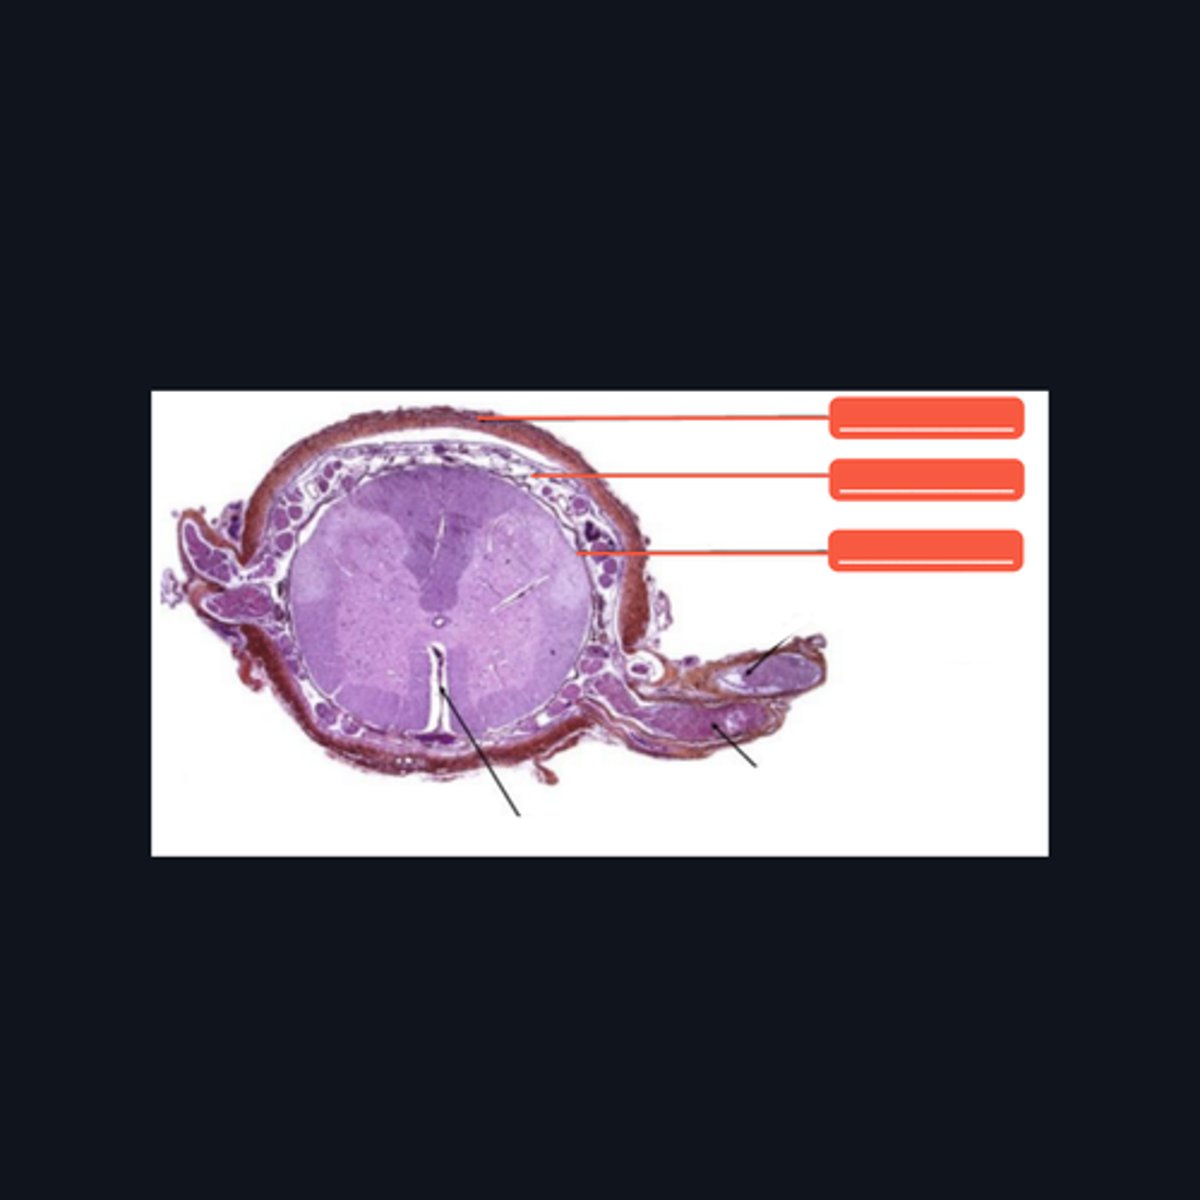

Identify the pointed region in the spinal cord

(1) Ventral Horn, (2) Dorsal Horn

Identify the pointed regions of the gray matter of the spinal cord

(top to bottom)

Dura mater

Subarachnoid space

Pia mater

Identify the pointed structures

White matter

(top to bottom)

Ventral median fissure

White matter

Ventral horns

Central Canal

Central commissure

Dorsal midline sulcus

Dorsal horns

Identify the parts of the sacral region of the spinal cord.